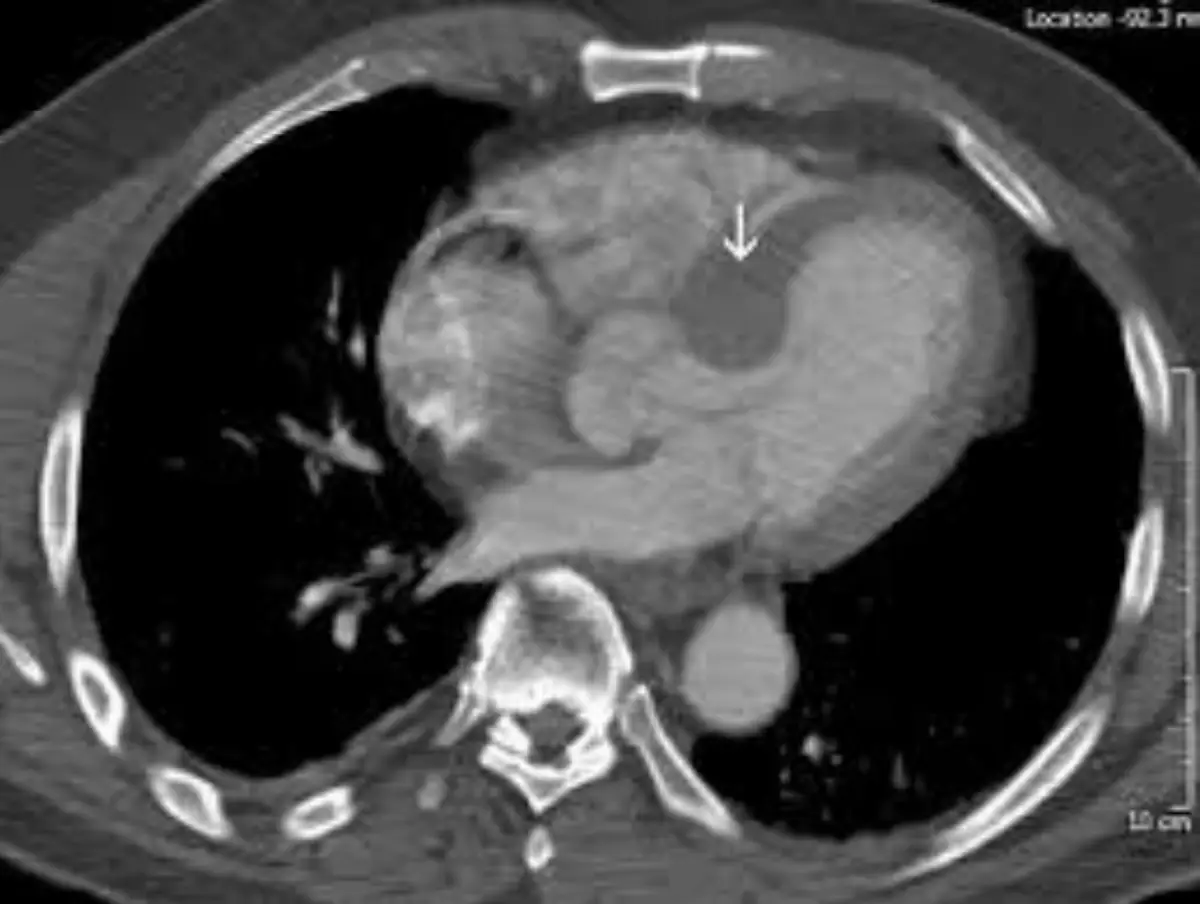

病人64歲家庭主婦,近三個月來有間歇性胸悶及運動性呼吸困難。病人有氣喘及高血壓10年病史,規則 服用Ipratropium或Furosemide + Aldactone + Digoxin + Aspirin。事實上病人過去10年前就有類似症 狀,再多加服用上列藥物,也就改善。只是近月來全身倦怠,食慾不振,上腹微痛及體重減輕七公斤,乃 於七月廿六日住院診療。病人Height: 156 cm Weight: 68kg ; T/P/R:37.1/88/16;。 BP: 110/73 mmHg。理學檢查發現心臟大小正常,規則律跳,唯心尖處(Apical area) 有雙峰脈波bifid pulse) 及在左上 胸緣及心尖處有Gr 4/6 Pansystolic murmur,下肢有2度浮腫,但其他器官並未有異常。血球檢 查:WBC,10.14k/uL; RBC, 4.79 M/uL; Platelet, 169K/uL。血液生化結果: Albumin, 4.2 gm/dL; T-Bil, 0.86 mg/dL; BUN, 16.8 mg/dL; Cre1.0 mg/dL; ALT, 90 U/L。其心電圖及胸部X光如圖。經心導管檢查: 大動脈 血壓, 142/68 mmHg; 左心室出口部( LVOT), 158/28 mmHg; 左心室心尖部, 198/32 mmHg. 其左心室造影 及Cardiac CT如圖。請問病人的正確心臟診斷是: 圖片描述 圖片描述 圖片描述 圖片描述

4. Cardiac CT

– 橫截面可見心室中段室壁明顯肥厚,腔內呈狹窄;心尖部壁薄而凸出(箭示),即心尖動脈瘤(apical aneurysm)。